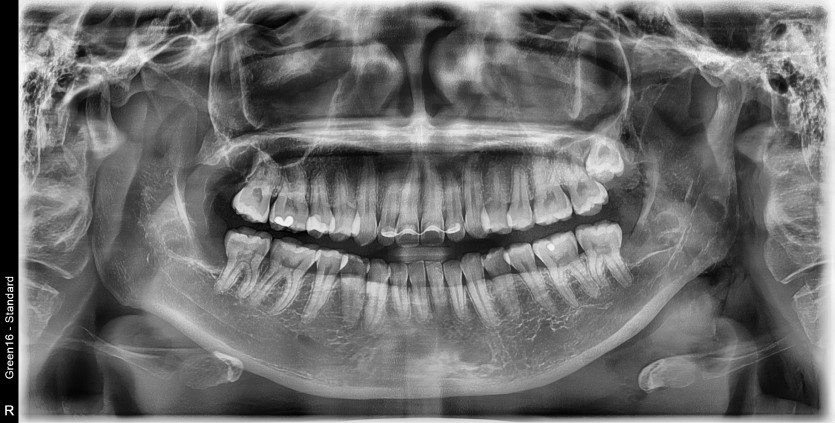

#18,38,48 사랑니 발치

구강 외과 전문의가 당일 발치했습니다.